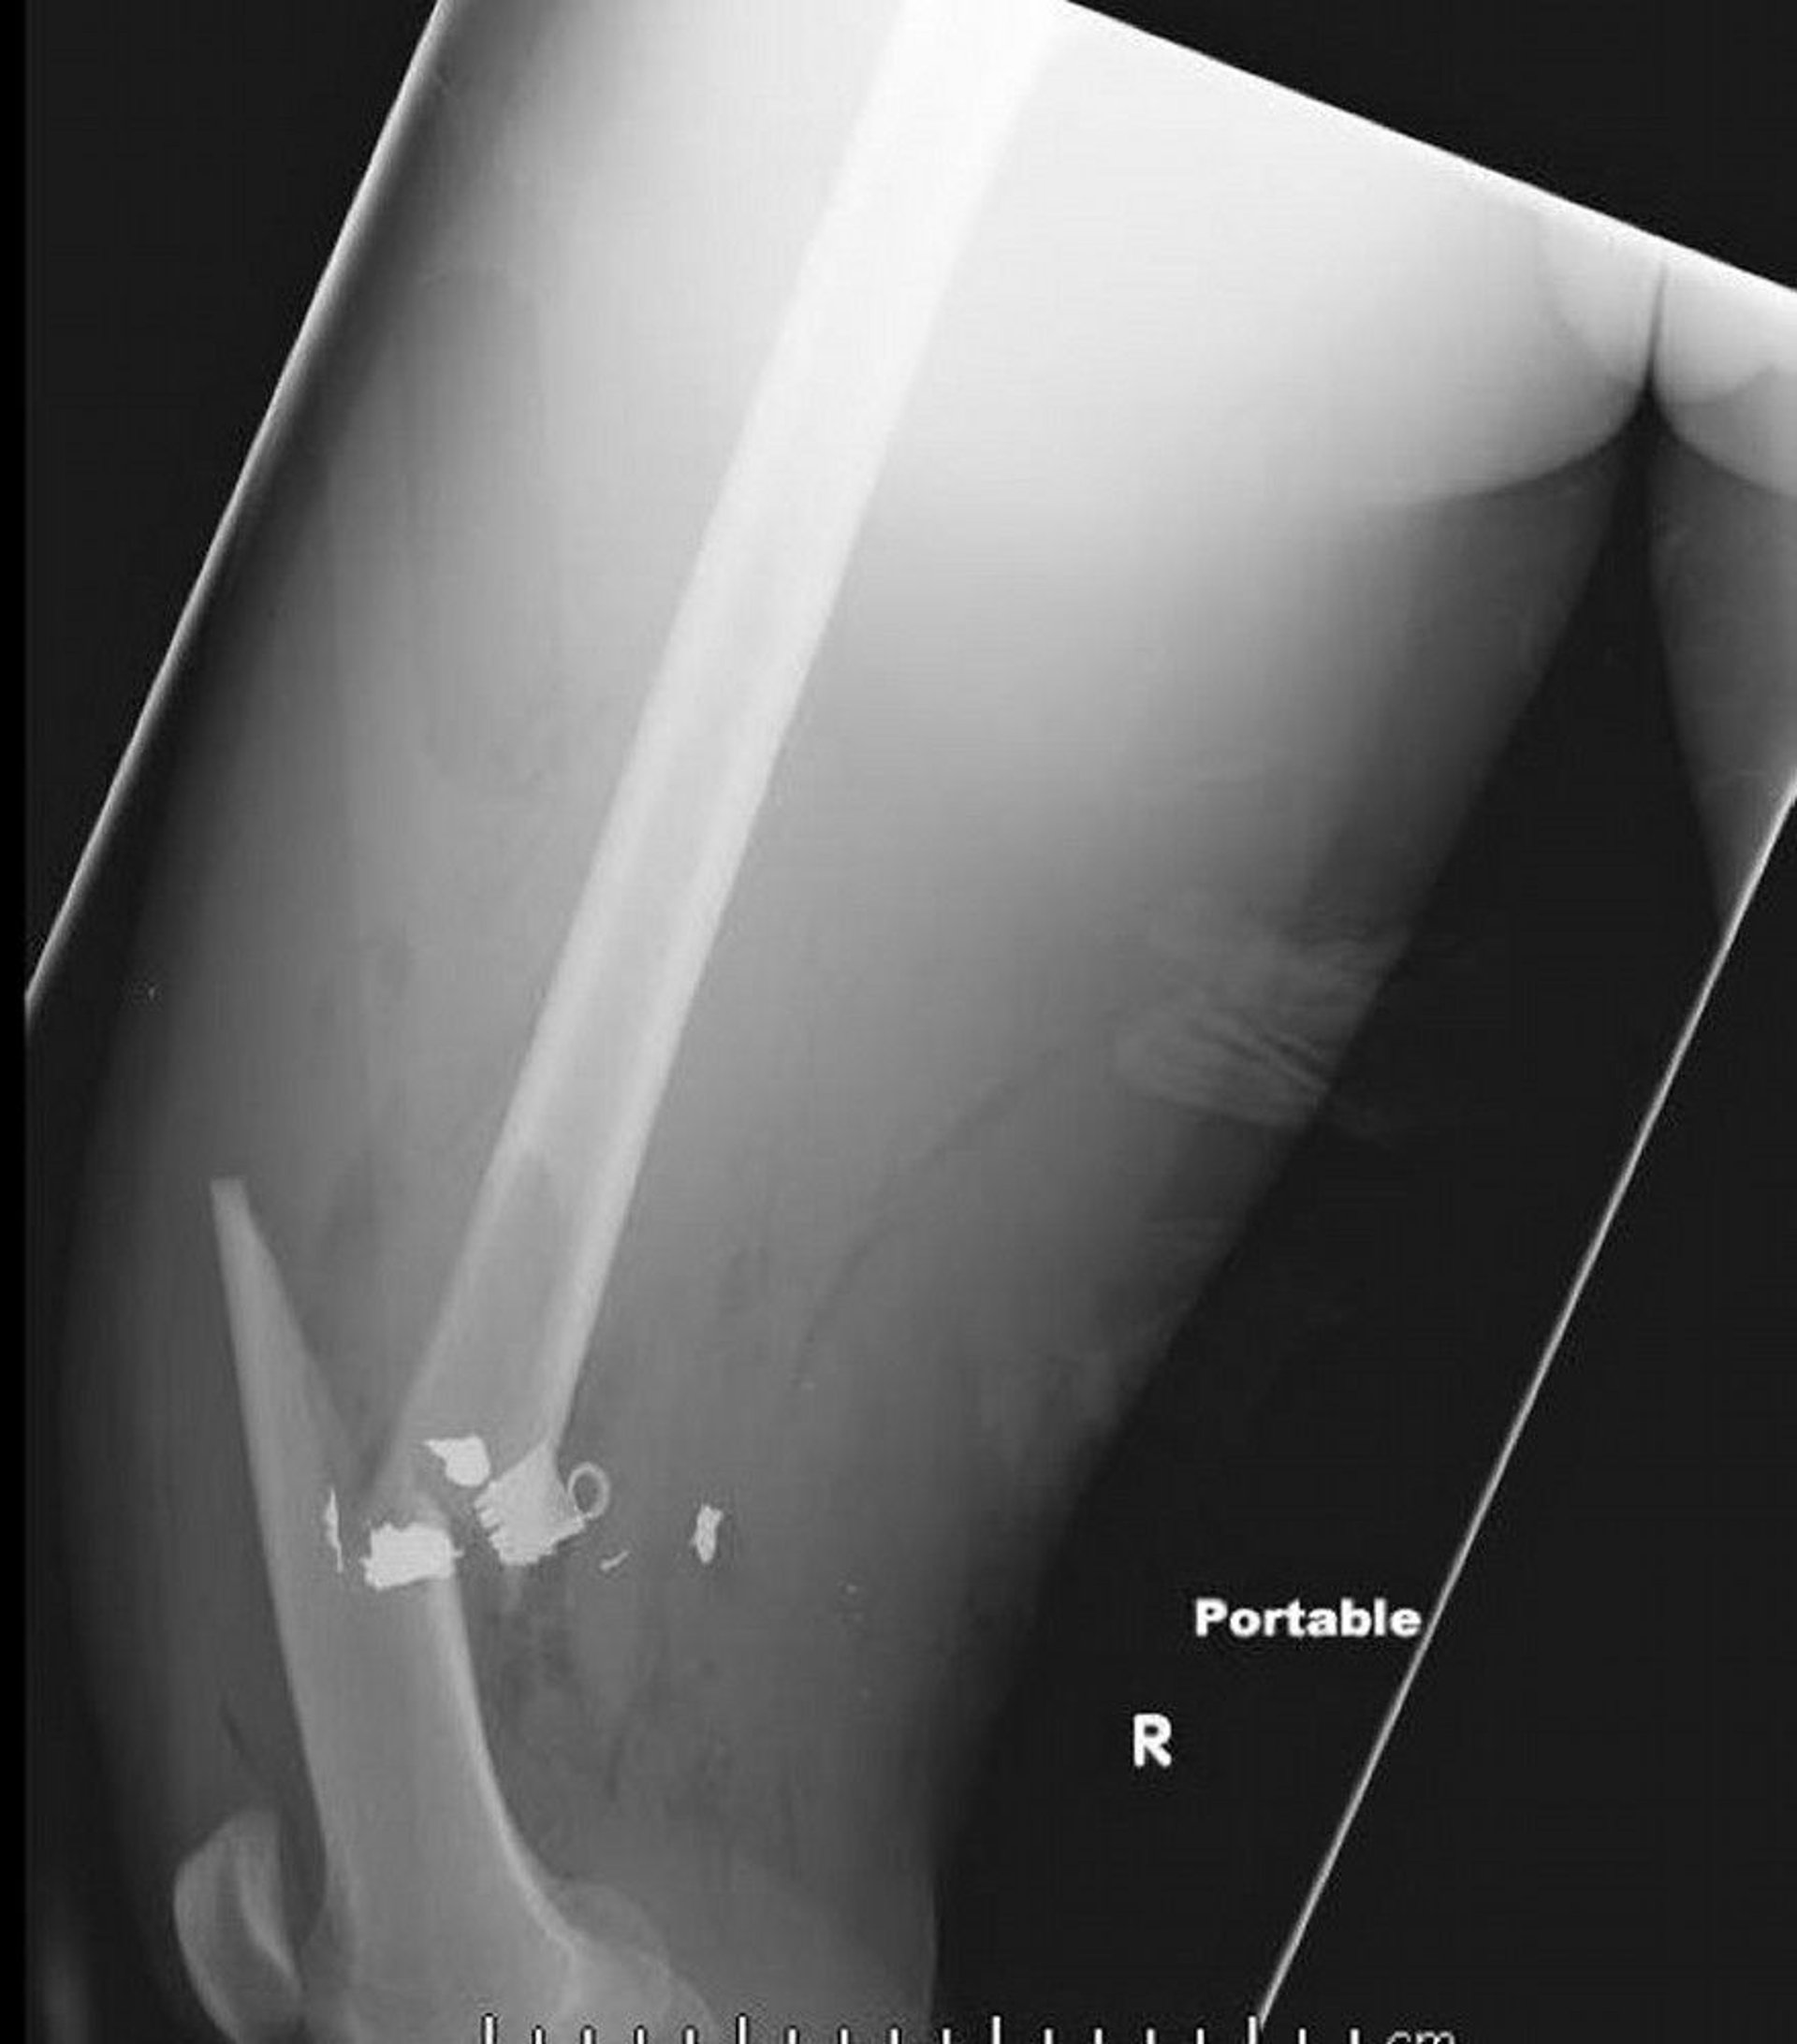

This lateral femur radiograph shows a midshaft femur fracture with soft tissue air and retained metallic density foreign bodies.